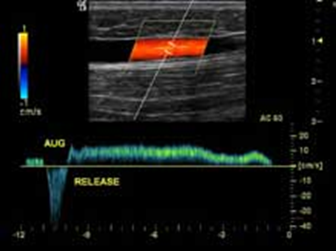

- Siêu âm Doppler đo tốc độ dòng máu và xem xét cấu trúc các tĩnh mạch chân, đánh giá tình trạng và mức độ suy giãn của các tĩnh mạch. Đây là xét nghiệm đơn giản, thuận tiện, dễ thực hiện và có độ chính xác cao.